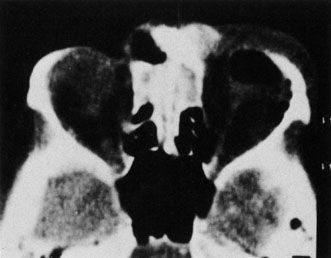

CT is particularly useful for imaging orbital and subperiosteal abscesses. Because the periorbit is not adherent to the orbital walls except at the suture lines, an abscess lifts the periorbit, creating a convexity in the orbital periosteum (Fig. 16). Usually subperiosteal abscess formation occurs adjacent to the involved sinus,25,64 but occasionally it occurs at a remote location such as the superolateral orbit.65 Gas may be found within a subperiosteal abscess or within the orbit, arising either from gas-forming bacilli or free communication with sinus air or from prior trauma (Fig. 17). 57,66 CT cannot accurately predict whether a subperiosteal mass represents exudate, inflammatory transudate, or hematoma.67,68

Fig. 16. Computed tomography showing subperiosteal abscess formation. Note elevation of orbital periosteum and convexity as pus elevates periorbit from the medial orbital wall.